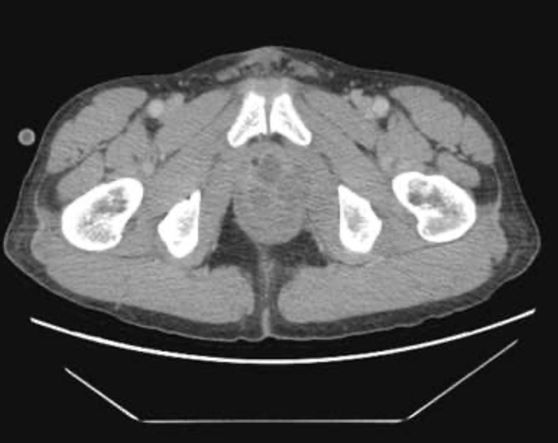

Abscess tuyến tiền liệt là một biến chứng của viêm tuyến tiền liệt cấp do vi khuẩn. Tỷ lệ abscess tuyến tiền liệt hiện nay rất thấp do việc sử dụng kháng sinh thích hợp. Cần nghĩ đến khi bệnh nhân có tiền căn đái tháo đường, HIV hay điều trị kháng sinh ban đầu không đáp ứng sau 48h. Để chẩn đoán xác định cần thực hiện các phương tiện chẩn đoán hình ảnh như siêu âm qua ngã trực tràng và CT scan. Dấu hiệu của abscess trên siêu âm là hình ảnh vùng echo kém. CT scan sẽ cung cấp chính xác vị trí, kích thước ổ abscess để hỗ trợ trong việc lên kế hoạch điều trị cũng như xác định có tổn thương lan rộng ra khỏi tuyến tiền liệt hay không.

Hình 2: hình ảnh abscess tuyến tiền liệt trên CT scan